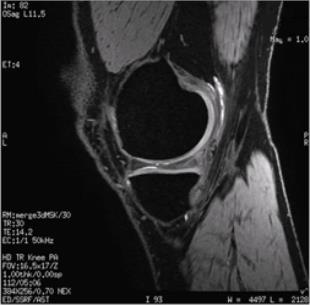

MERGE is a 2D or 3D fast GRE pulse sequence that acquires multiple echoes at several different TEs and then averages those echoes to form a single T2*-weighted image. MERGE uses a larger receive bandwidth (31.25 kHz), which reduces chemical and susceptibility artifacts and improves image quality.

Use MERGE in the C-spine to minimize susceptibility and chemical shift artifact and in the knee for high resolution extremity imaging when increased T2* weighting is desired.

Figure 1. Sagittal 3D MERGE knee